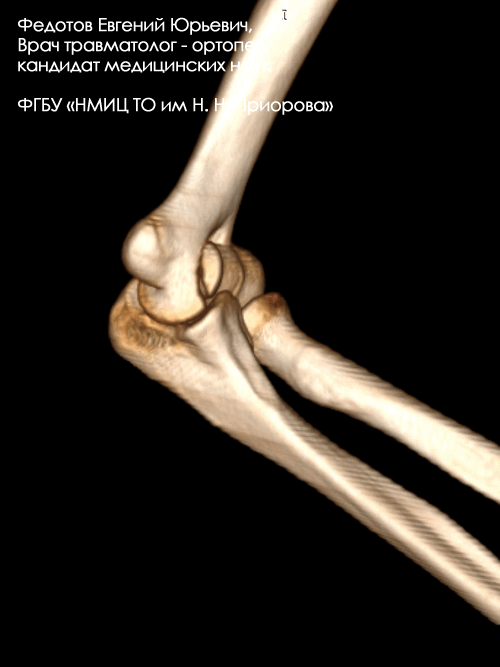

Пациентка с тяжелым внутрисуставным переломом нижнего отдела (мыщелков) плечевой кости с тяжелым повреждением локтевого сустава.

Рентгенограмма до операции.

Выполнена операция: металлоостеосинтез плечевой кости современными пластинами LCP, анатомия локтевого сустава полностью восстановлена.

Гипсовая повязка после операции не применялась, сразу разрешена разработка движений в суставах конечности. Результат через 5 дней после операции. Швы еще не сняты, виден отек, кровоподтеки на конечности после перелома. Уже видна хорошая функция конечности.

Результат через 3 мес. после операции. Функция конечности полностью восстановлена.